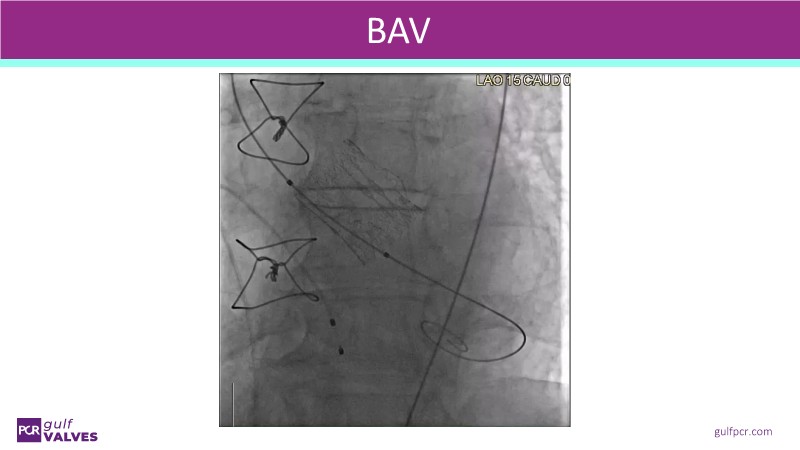

This session helps you anticipate and address complex scenarios such as mitral valve-in-valve, TAV-in-SAV, and valve-in-valve-in-valve procedures. Learn from expert case discussions that explore procedural strategies, technical challenges, and best practices to optimize outcomes in redo structural heart interventions.

- To understand procedural strategies and challenges in complex redo scenarios using SAPIEN 3 Ultra RESILIA